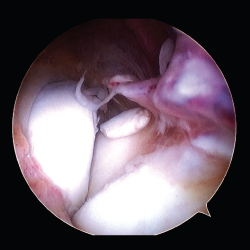

Las osificaciones heterotópicas limitan la movilidad, especialmente en las fracturas de la cabeza del radio por su situación anatómica y la complejidad del mecanismo de pronosupinación (Figura 1).

Figura 1. Calcificación heterotópica posfractura de la cabeza del radio. A: imágenes de la fractura; B: calcificación heterotópica en cuello; C: imagen tras la exéresis.